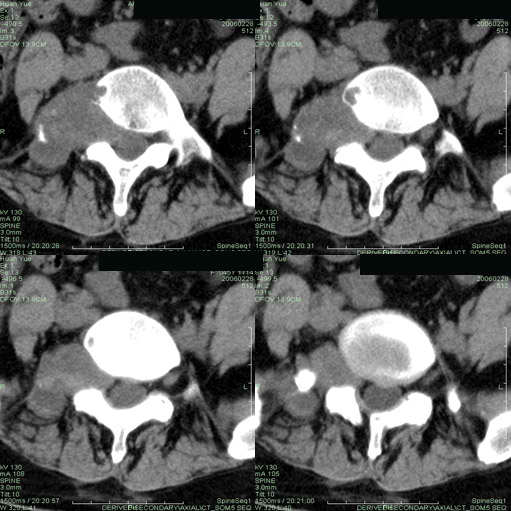

以下是引用听蝉观竹在2006-3-5 23:09:00的发言:[br]这个病例不考虑神经源性肿瘤,首先考虑转移瘤,因为它不是受压造成骨质吸收,而是从骨骼的松质部分由中心向外破坏的,不仅仅是横突,而且同侧椎弓根也破坏了。[br]神经源性肿瘤-----受压造成骨质吸收。[br]转移性肿瘤------从骨骼的松质部分由中心向外溶骨破坏,多见椎弓根也破坏。

以下是引用徐大夫在2006-3-5 20:32:00的发言:[br]骨缺损区边缘有硬化,结合部位,考虑神经源性良性肿瘤。